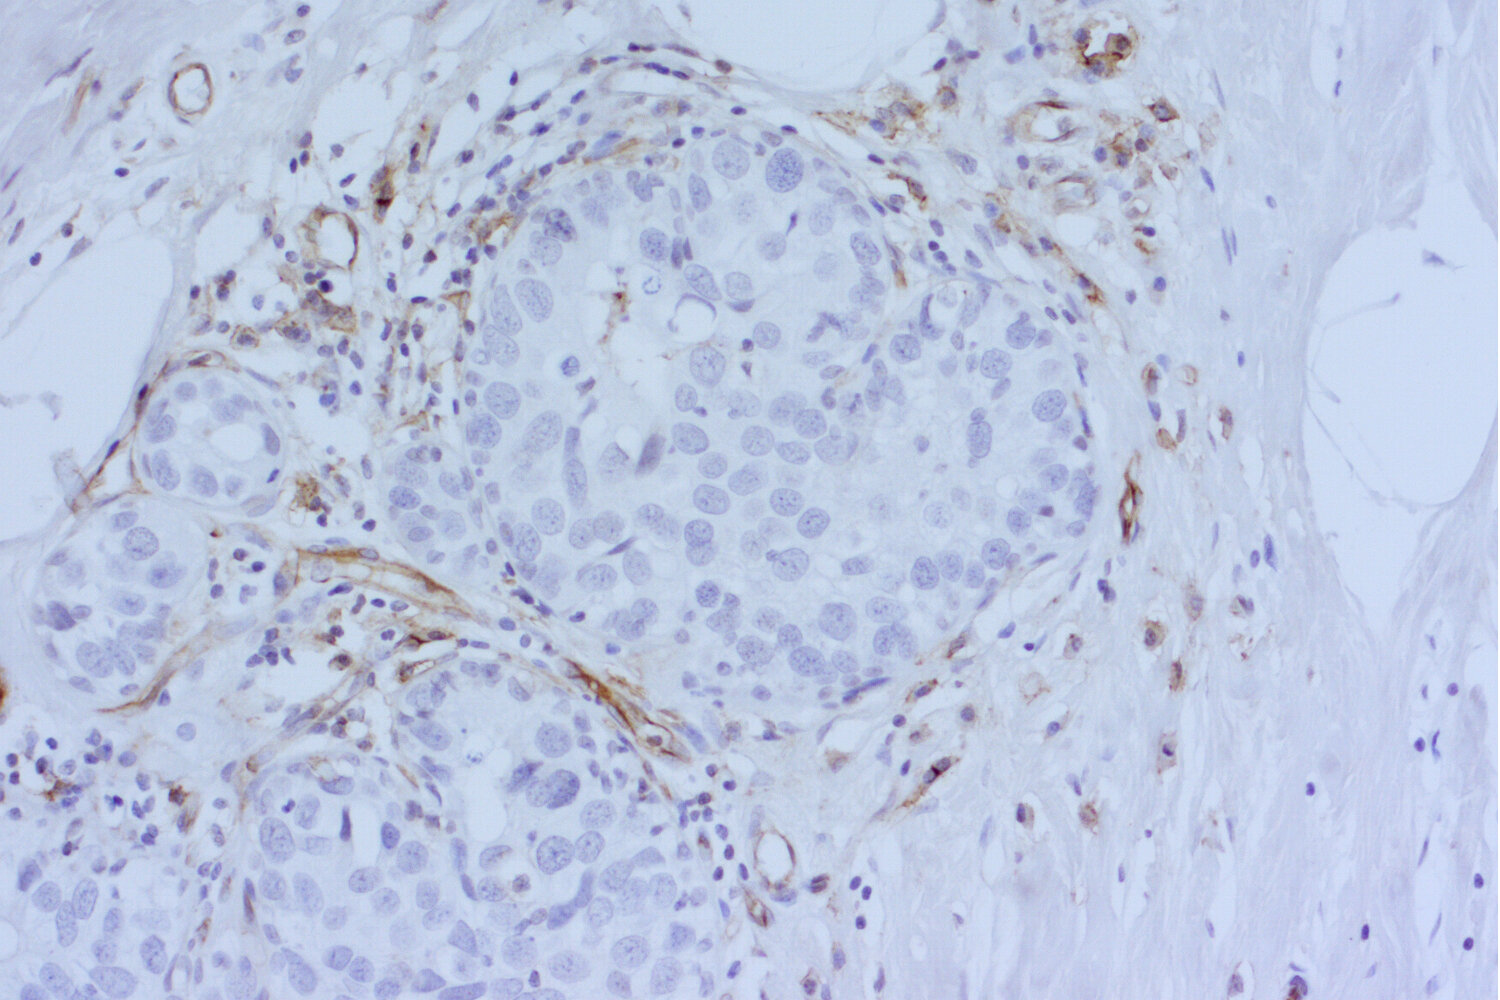

Visualization of blood vessels in a human invasive ductal breast cancer section using anti-CD31 antibody.

IHC-P (FFPE): 1 : 200 up to 1 : 500 gallery

Immunohistochemistry (IHC-P) of formalin fixed, paraffin embedded (FFPE) tissue (some antibodies require special antigen retrieval steps, please refer to the ”Remarks” section). Immunoreactivity is usually revealed by fluorescence or a chromogenic substrate.

The Journal of clinical endocrinology and metabolism (2021) 1061: 26-41. HS-351 004 IHC-P (FFPE); tested species: human

The Journal of clinical investigation (2019) : . HS-351 004 IHC-P (FFPE); tested species: human